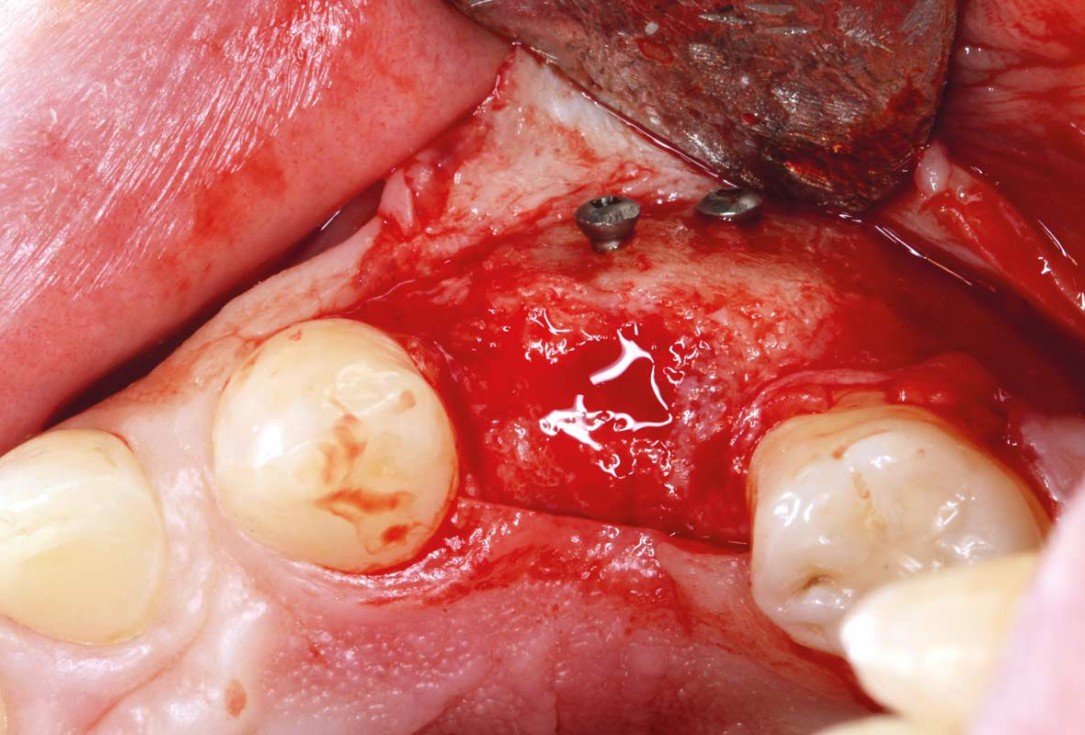

3/11 - Fixation of allogenic bone block, maxgraft® blockRidge reconstruction with maxgraft® block in the posterior maxilla - Dr. A. Puišys